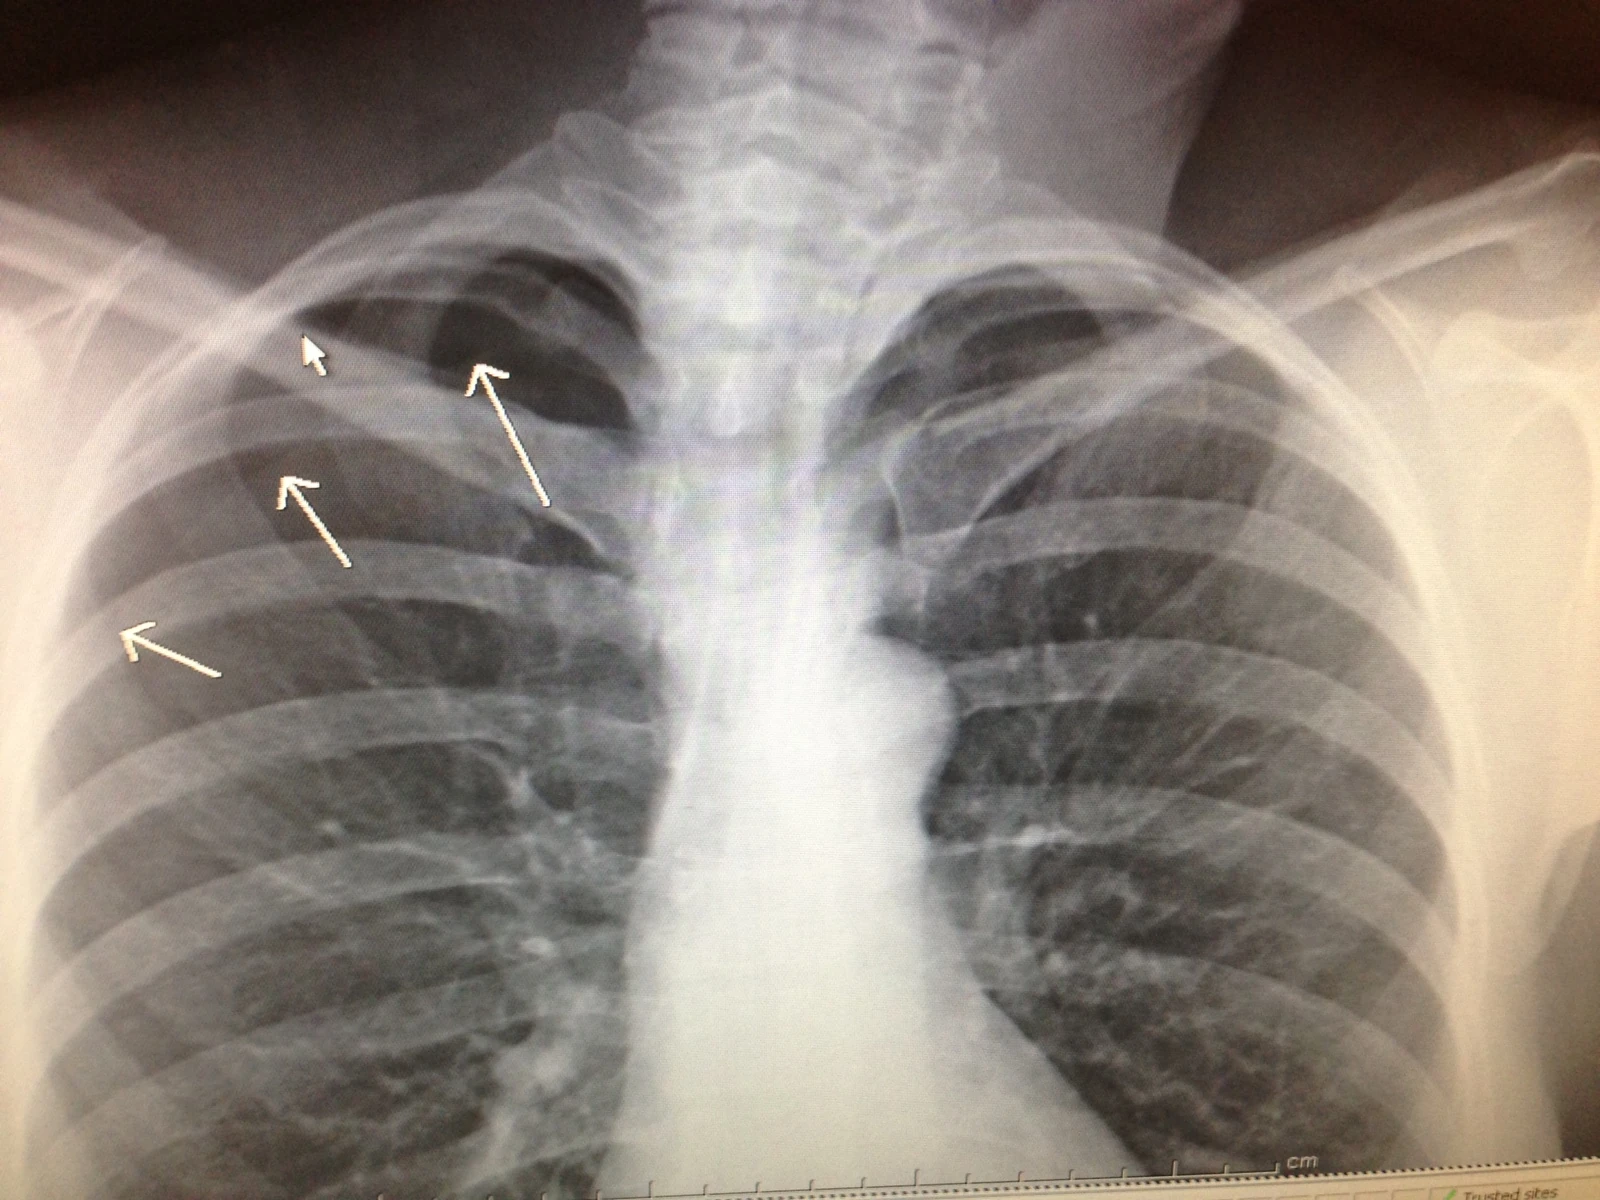

Short update. I spent all day bouncing around between medical buildings. In the meantime, Catherine rode her bike to the urgent care clinic the morningand next thing I know, Trudi was taking her to the hospital where she had to have surgery because of her crash. I guess her lung collapsed and didn’t refill, allowing air/fluid behind it. So, she is in the hospital until Monday with a tube in her chest. I have a huge tear in my rotator cuff cartilage that won’t repair on its own, so I need surgery too. More later. Okay, I have more stuff to do, but didn’t see any bike racing today, which is a drag.

I’m so sorry for the bad luck both of you had. No fun. You have one gnarly looking collar bone in your x-ray. How many times have you broken that or was it once really bad?